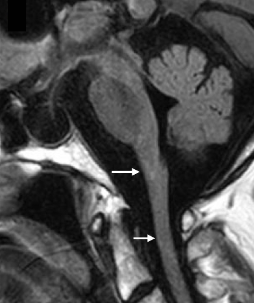

- Atrophy and changes in signal intensity in the cerebellum, medulla oblongata, and upper spinal cord, with variable supratentorial periventricular white matter abnormalities4

- A pattern of prominent atrophy involving the medulla oblongata and cervical spinal cord with sparing of the lower pons (ie, “tadpole sign”)8,53